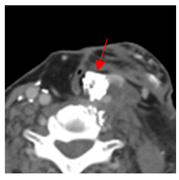

| 3 | 25–50 | 1716 | ![]() Axial CT image shows a mostly necrotic tumor in the right neck. | ![]() Axial CT image obtained 1 day after injection shows the NBTXR3 nanoparticles (arrows) in the tumor with a small amount of leakage into the surrounding soft tissues. |